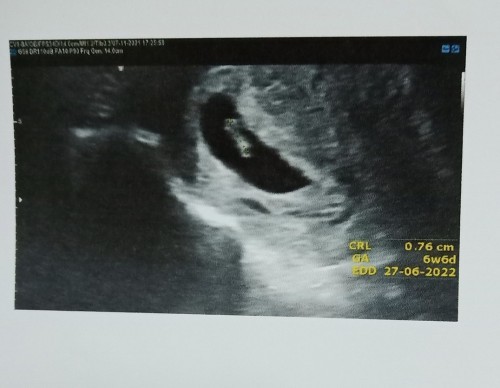

แม่ๆเจอน้องกี่วีคคะบ้านนี้เจอน้อง6w6dมาพร้อมเสียงหัวใจเลย😊😊😊